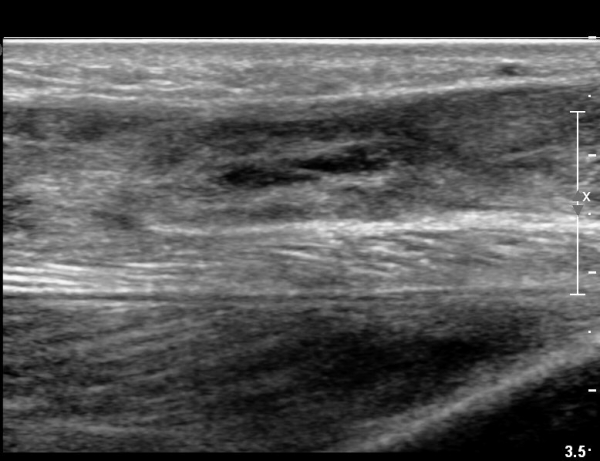

¾ÆÅ³·¹½º°Ç Àú¿¡ÄÚºÎÁ¾ÀÌ °¨¼ÒµÇ°í  ÆÄ¿­ºÎÀ§ Àú¿¡ÄÚ°¡ È£ÀüµÇ¾î

°ÇÀÇ ¼¶À¯¼º¾ç»ó(fibrillar pattern)ÀÌ È¸º¹µÇ°í ±¹¼ÒÀû ¿¬°á¼º ¼Ò½ÇÀÌ »ç¶óÁü(»çÁø 9, 10, 11, 12).